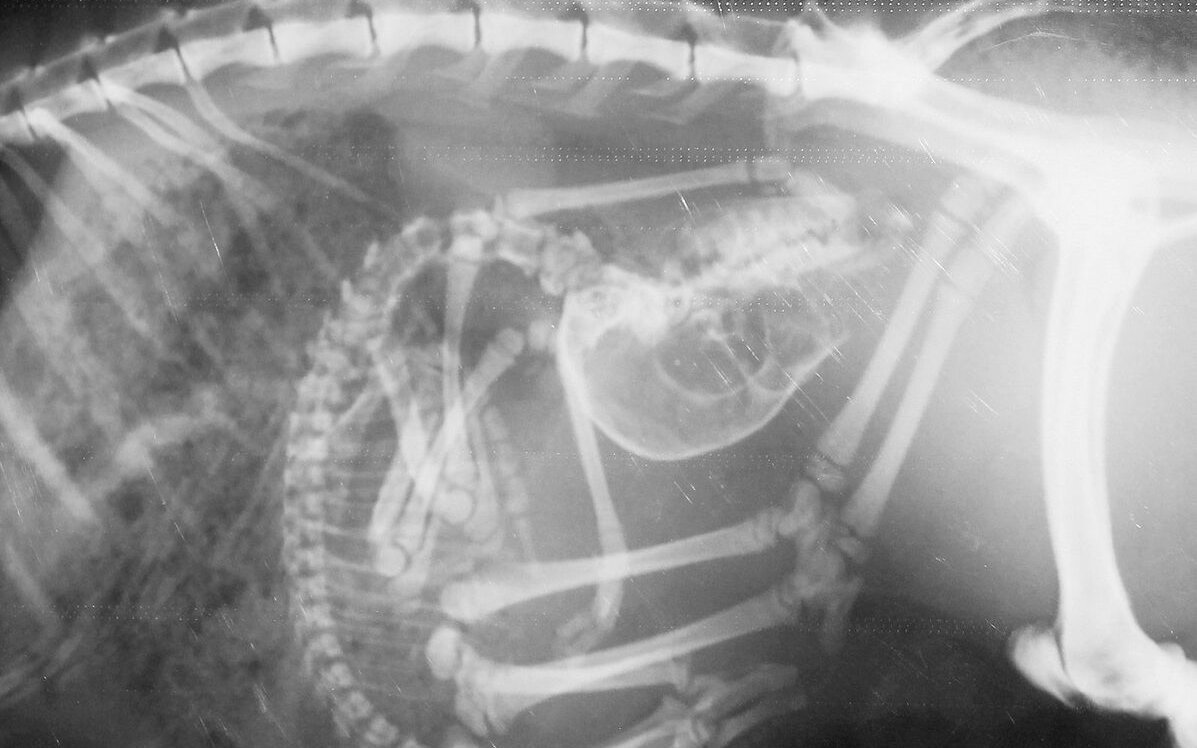

Erstaunlich, das Gerippe eines Seepferdchens! Wie ein Kunstwerk zeigen sich die Knochen, die der Bezeichnung Knochenfische alle Ehre machen. Wundersam wirkt das filigrane Schlangenskelett. Im Röntgenraum der Tierklinik im Basler Zoo wird rasch klar, wie komplex die Arbeit eines Zootierarztes ist. Er muss die Röntgenbilder zahlreicher verschiedener Arten interpretieren. Doch die Schwierigkeit beginnt schon vorher. Wie bekommt man Tiere, vom Seepferdchen bis zum Geparden, auf den Röntgentisch?

Dr. Christian Wenker ist froh über die Möglichkeit, Tiere röntgen zu können. Der leitende Veterinär im Basler Zoo erklärt: «Dank dem bildgebenden Verfahren haben wir in der Zootiermedizin ein rasches Resultat.» Bei Blut- und Kotuntersuchungen müsse bis am nächsten Tag gewartet werden. Schnelles Handeln ist in der Zootiermedizin wichtig. Zeigen Tiere Krankheitssymptome, liegt ein gravierendes Problem vor. Sie verbergen Unwohlsein, denn in der Natur werden schwächelnde Tiere durch Feinde eliminiert.